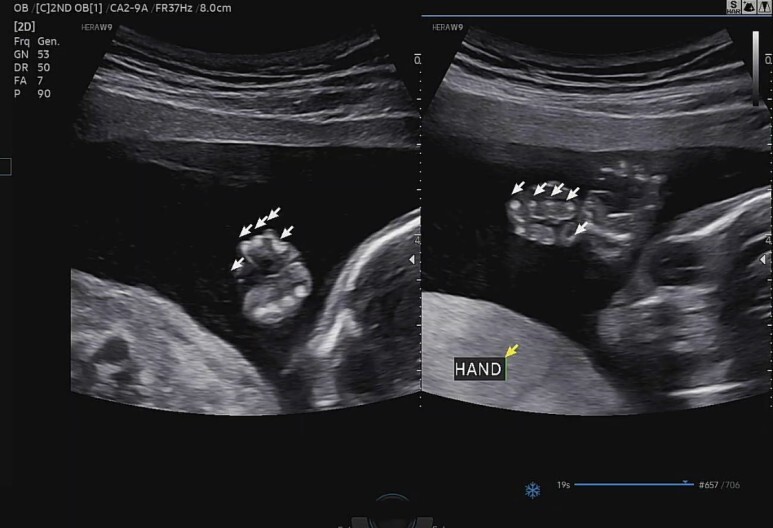

양 손가락도 확인. (HAND)

귀엽..